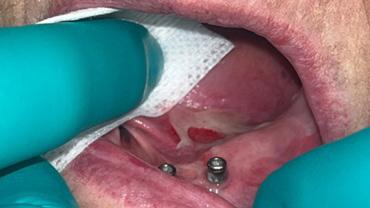

In February of 2024, a month after delivery of both prostheses, the patient reported for a denture adjustment

due to pain and discomfort. Upon evaluation, the patient had erosive lesions throughout her oral cavity including geographic tongue that were not consistent with pressure spots from her overdenture, as seen in figures 3-6.

It was determined that the patient could be having type IV hypersensitivity reaction to her new prostheses, or an immune-mediated reaction to a systemic condition. These findings were discussed with Dr. Kathleen Higgins in the OU Oral Pathology department where she intra-orally evaluated these lesions. She encouraged me to prescribe a magic mouth rinse to help alleviate underlying conditions, including an immune-mediated reaction.

FIGURE 5

FIGURE 6